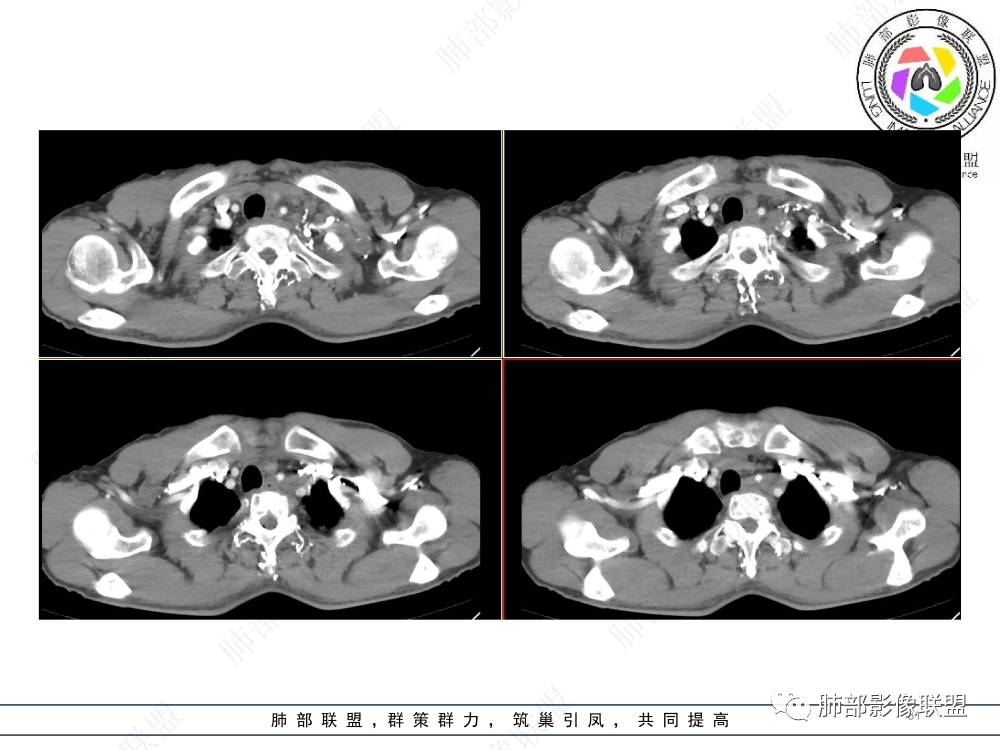

2.影像表现:前上纵隔较大肿块,密度不均,形态不规则,边界不清,有结节样突起,脂肪间隙显示不清。病灶侵犯左无名静脉及上腔静脉,其中左无名静脉闭塞(胸背部侧支循环明显,亦表明回流受阻)。增强后轻中度不均强化。坏死边界欠清晰。可见心包积液,提示心包受侵犯。右侧上叶及纵隔胸膜下结节影,疑胸膜肺转移可能。胸骨柄后缘皮质不完整,疑骨质破坏(未提供骨窗及矢状位图像)。左锁骨上可见肿大淋巴结。